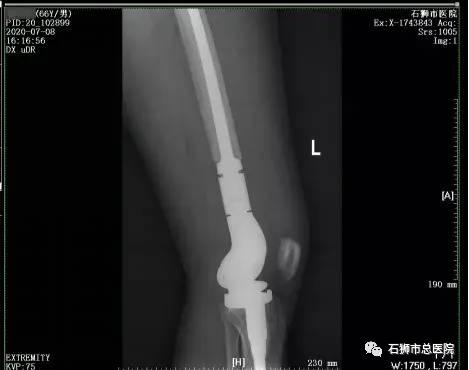

不仅如此,骨科还与上级医院建立合作关系。2019年11月起,与厦门大学附属福州第二医院建立骨科联盟关系。从此,骨科可以在专家的指导下,进行骨肿瘤、骨盆骨折、双膝关节置换等高难度类型手术。截止目前,厦门大学附属福州第二医院专家已在市总医院进行200多场大大小小的手术,举办讲座18场,每周三、周四还有专家定期到石狮市总医院骨科坐诊、手术,在向市总医院“输血”的同时,也让市总医院骨科医生有“造血”的本领,更重要的是石狮市民可在石狮接受上级专家诊疗。